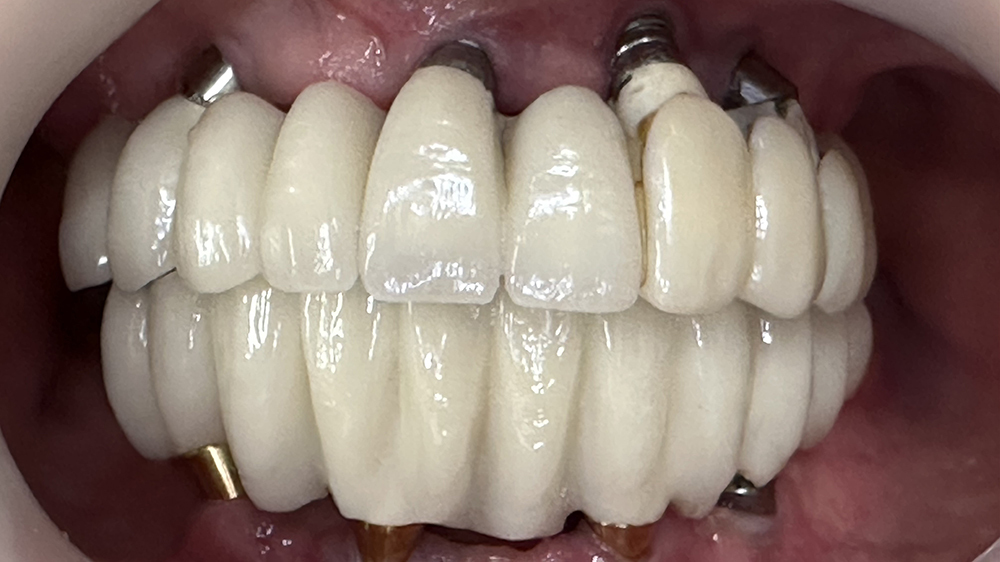

症例4

Before

After

KYさん、50代男性

治療の期間・回数:約6か月

​治療の価格:約3,300,000円

治療内容:この方は40代で歯がほとんどなく、12年前に上あごに6本、下あごに4本のインプラントを使って、手術当日に仮の歯を入れる「即時荷重」で治療しました。

上の歯は当初、安価な金属のフレームに入れ歯の歯を並べたものを装着しました。

しかし、強い歯ぎしりのため、上の歯は3年で壊れ、修理して再装着しても2年でまた壊れてしまいました。そこで、丈夫なコバルトクロムのフレームにフルジルコニアの歯を接着した最高強度のブリッジに作り替え、見た目を良くするため人工の歯ぐきを付けました。

このブリッジは高価な技工物ですが、約80万円の原価で製作しました。

再装着してから7年経ちますが、今のところ問題なく安定しています。